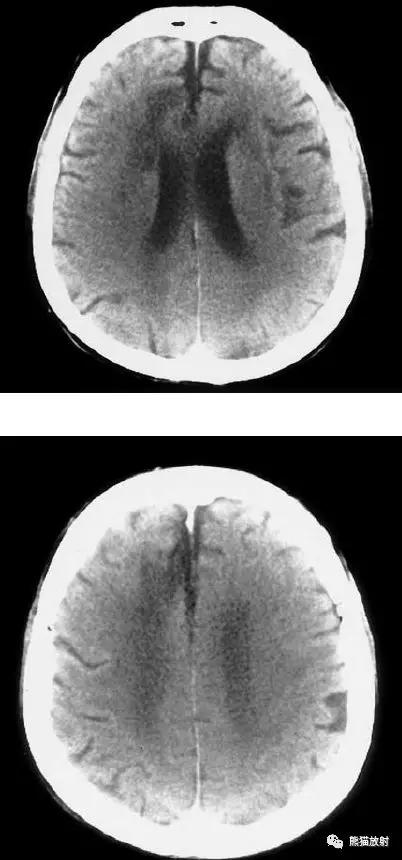

分水岭脑梗死(“Watershed” infarcts):右侧大脑前中动脉及中后动脉供血区之间梗死灶。

分水岭脑梗死:左侧深部和浅部大脑中动脉供血区之间梗死灶。

左侧尾状核头脑梗死;右侧外囊腔隙性脑梗死。

椎基底动脉区域的梗死:范围较广,非均质的低密度区域,累及脑干,小脑半球的前外侧以及颞叶的内后侧。

后颅窝梗死:脑桥、中脑、左小脑半球。

左侧及双侧丘脑梗死